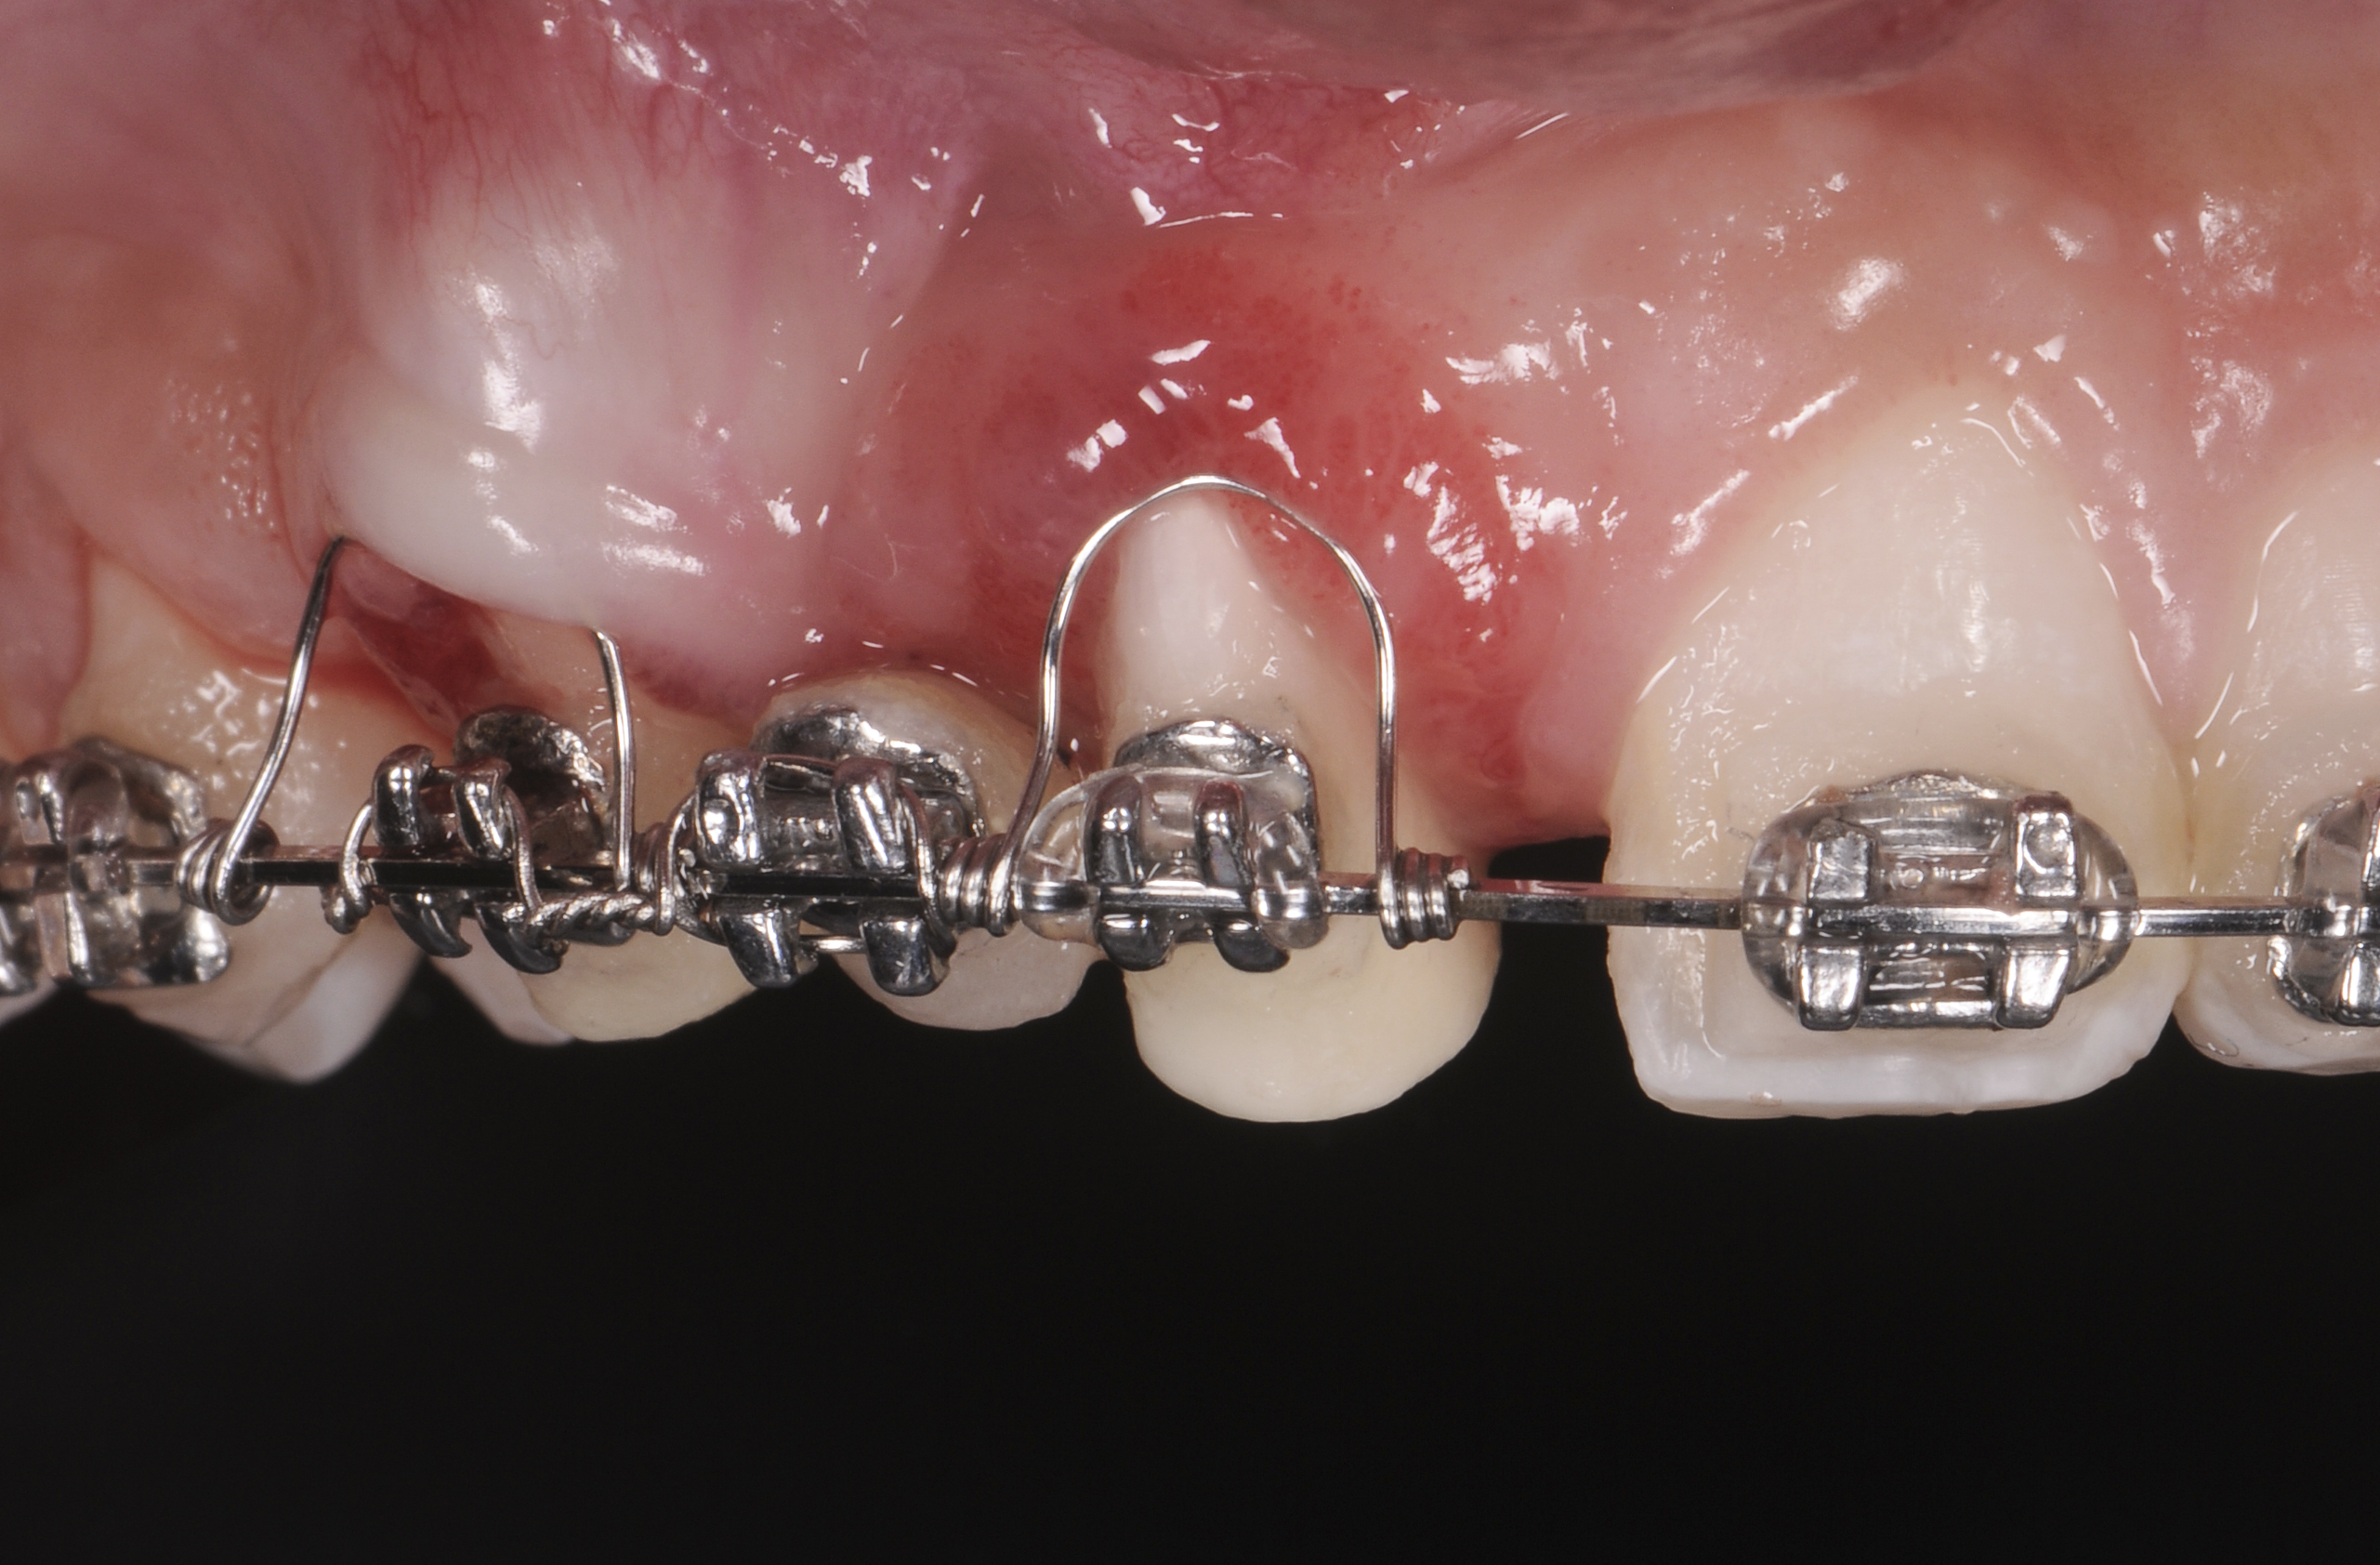

When forced eruption is completed, the teeth should be splinted for a 3-month stabilization period,30 which will allow mineralization of osteoid tissue and settling of the gingival remodeling process. The degree of forced eruption in the present case was such that extreme mobility precluded the use of a provisional restoration. Instead, a metal-reinforced direct composite splint extending from teeth Nos. 6 to 8 was fabricated in situ (Figure 8 and Figure 9). When compared with the preoperative condition (Figure 2), Figure 8 and Figure 9 depict the treatment progression with forced eruption. The restoration of adequate alveolar height was achieved while enhancing the soft-tissue architecture, and the everted sulcular epithelium on tooth No. 8 proceeded to develop keratinization. However, the pre-existing defect still manifested itself in the form of a residual cleft.

Successful outcomes with forced eruption require the establishment of treatment endpoints, which may include overcompensation beyond the desired soft- and hard-tissue changes. For the present case, achieving ideal gingival-alveolar socket architecture required force-erupting tooth No. 6 to the level of the apical third and tooth No. 8 beyond the confines of its alveolus. As the gingival sulcus is everted through the eruption process, a gingival red patch corresponding to the nonkeratinized sulcular epithelium may appear, as shown around tooth No. 8 in Figure 8 and Figure 9. This tissue will develop into keratinized gingiva when exposed to the oral environment.31,32 Additionally, when forced eruption of this magnitude is performed, there may be a tendency for lingual displacement that needs to be addressed with root-torquing orthodontic auxiliaries (Figure 6 and Figure 7).